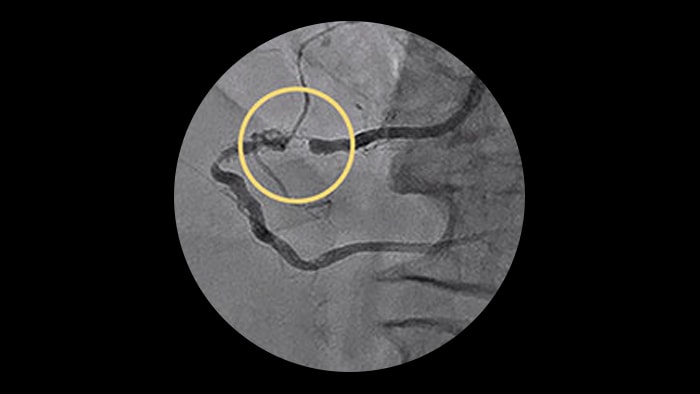

– Stent length is an independent predictor of in-stent restenosis and thrombosis.

– Stenting long segments with multiple and or overlapping stents may lead to injury to the vessel wall integrity.

– Diffuse CAD may be underestimated by evaluation with coronary angiography.